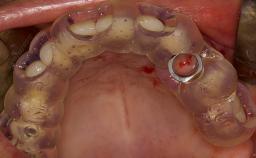

• list the indications for the lateral SFE technique

• describe the surgical treatment concept and steps for the lateral SFE technique and assess the prognosis of this procedure

• discuss the grafting materials used in lateral SFE and the indications for use of membranes